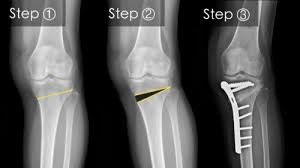

High tibial osteotomy (HTO) is a surgical procedure that realigns the knee joint by cutting and repositioning the tibia (shin bone). The procedure is often used to treat medial knee arthrosis, which can cause a bowlegged alignment that puts too much stress on the knee's inner compartment. HTO can also be used to correct varus or valgus alignment, knee instability, post-traumatic arthritis, and knee pain.

During the procedure, a wedge of bone graft or synthetic bone is placed on the medial side of the tibia and secured with screws and a plate, or a wedge of bone is removed from the outer side. HTO is usually recommended as a last resort after other non-surgical treatments have been tried.

However, HTO can also have complications, including infection, loss of correction, and nonunion. There's also a risk of lateral hinge fracture if the HTO is medially based, and a risk of peroneal nerve injury if it's laterally based. About 15% of patients may need to have the procedure redone, with hardware removal being the most common procedure.